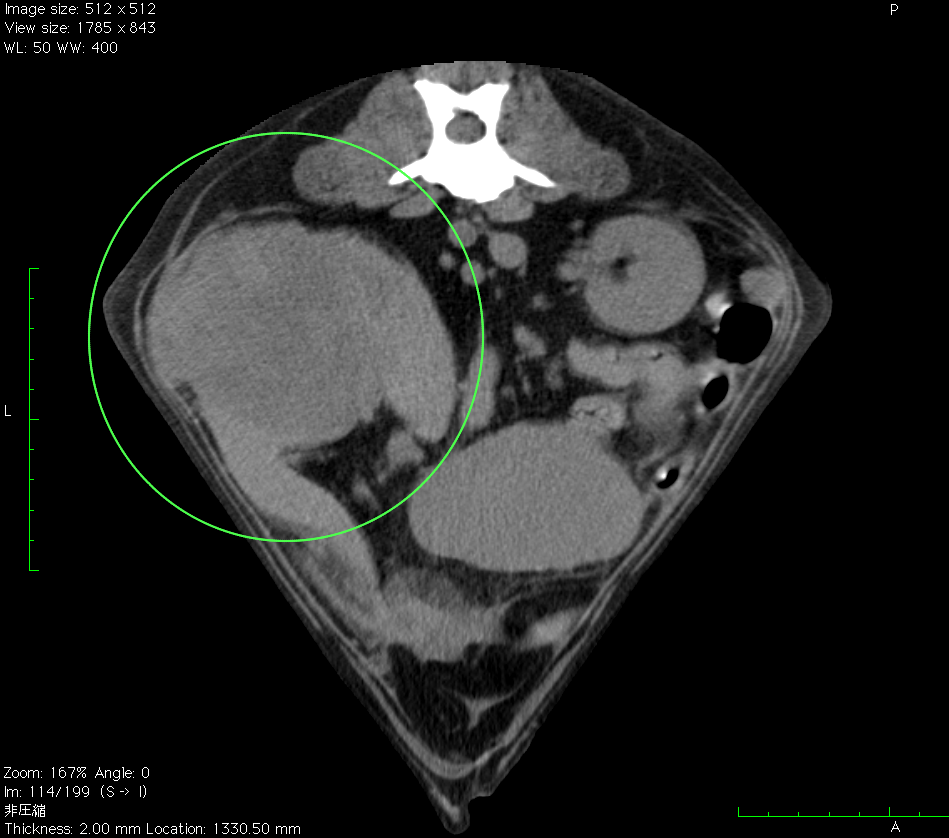

本院では、4列マルチスライスヘリカルCT装置(TOSHIBA Asteion4)を導入しました。

1回転で4断面の画像を取得することができ,0.75秒の高速フルスキャンを可能とすることで,肺野領域30cmの範囲を最速6秒以下でスキャン可能です。

従来の1列のCTより短時間で、被爆量の少ない、正確な検査が可能です。

●CT検査が有用な病気

・腹腔内病変

脾臓の血管肉腫